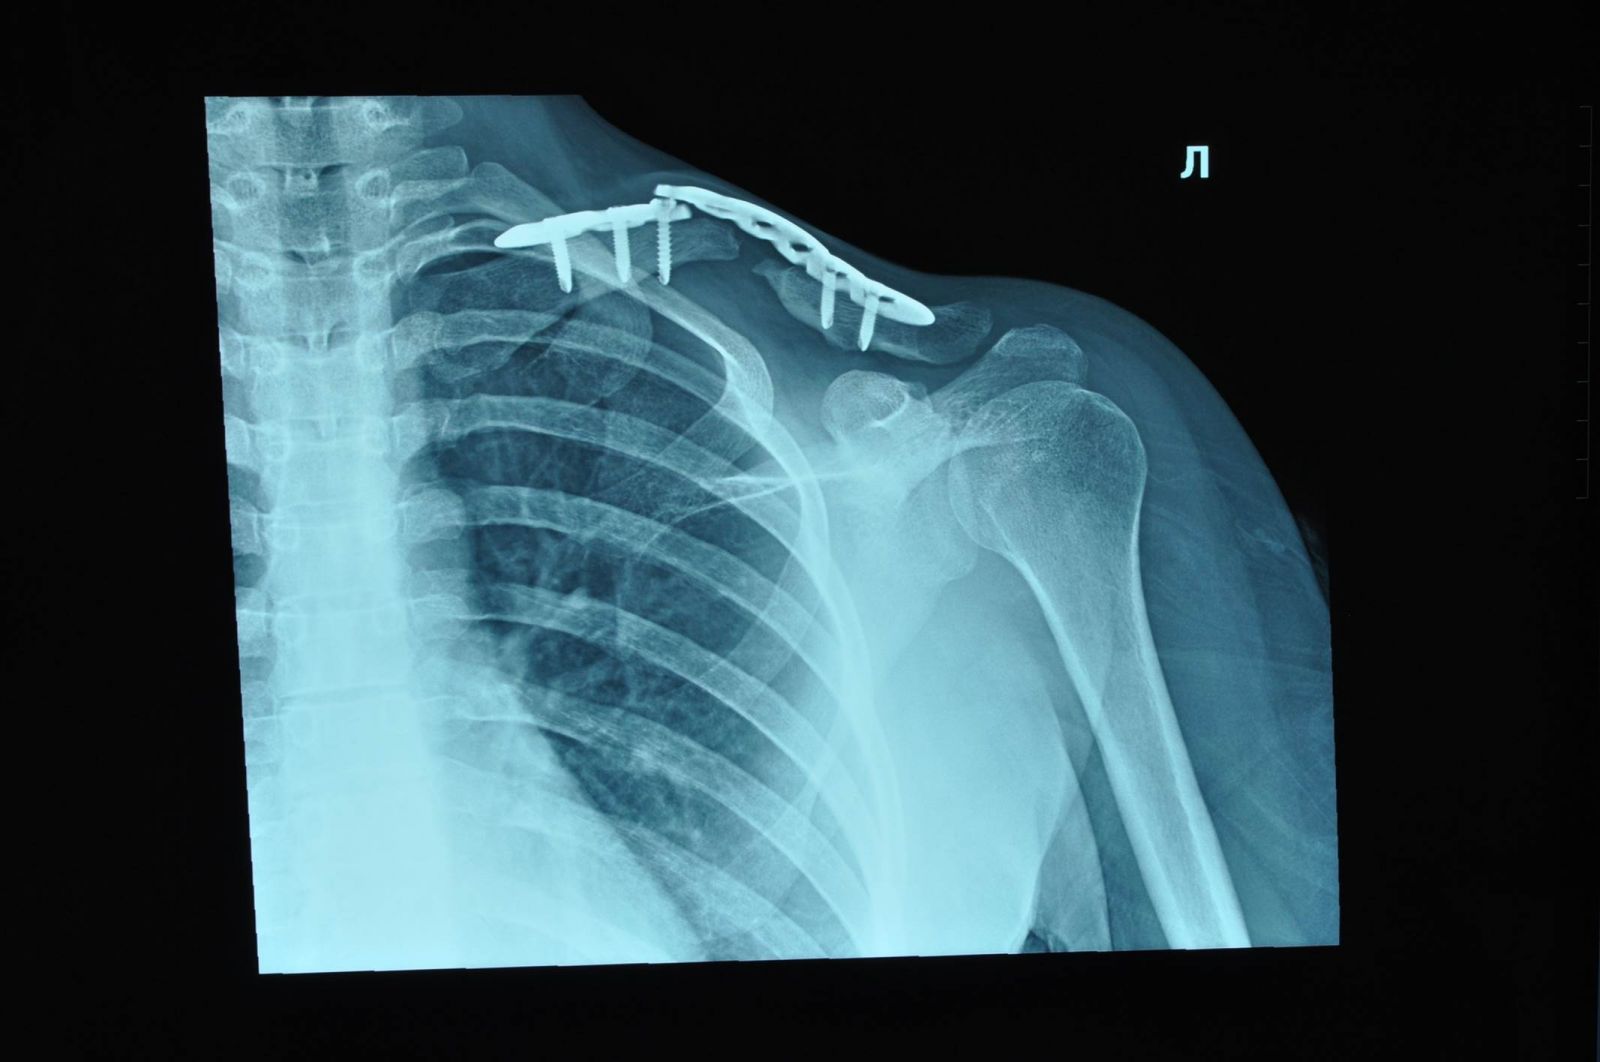

Рис.2. Пациентка, 31 год. 3 месяца после операции. Срастающаяся левая ключица после разрушения ложного сустава, костной пластики свободным кровоснабжаемым аутотрансплантатом, фиксации костных отломков пластиной и винтами. Рис.3. Пациентка, 31 год. 12 месяцев после операции. Срастающаяся левая ключица после разрушения ложного сустава, костной пластики свободным кровоснабжаемым аутотрансплантатом, фиксации костных отломков пластиной и винтами